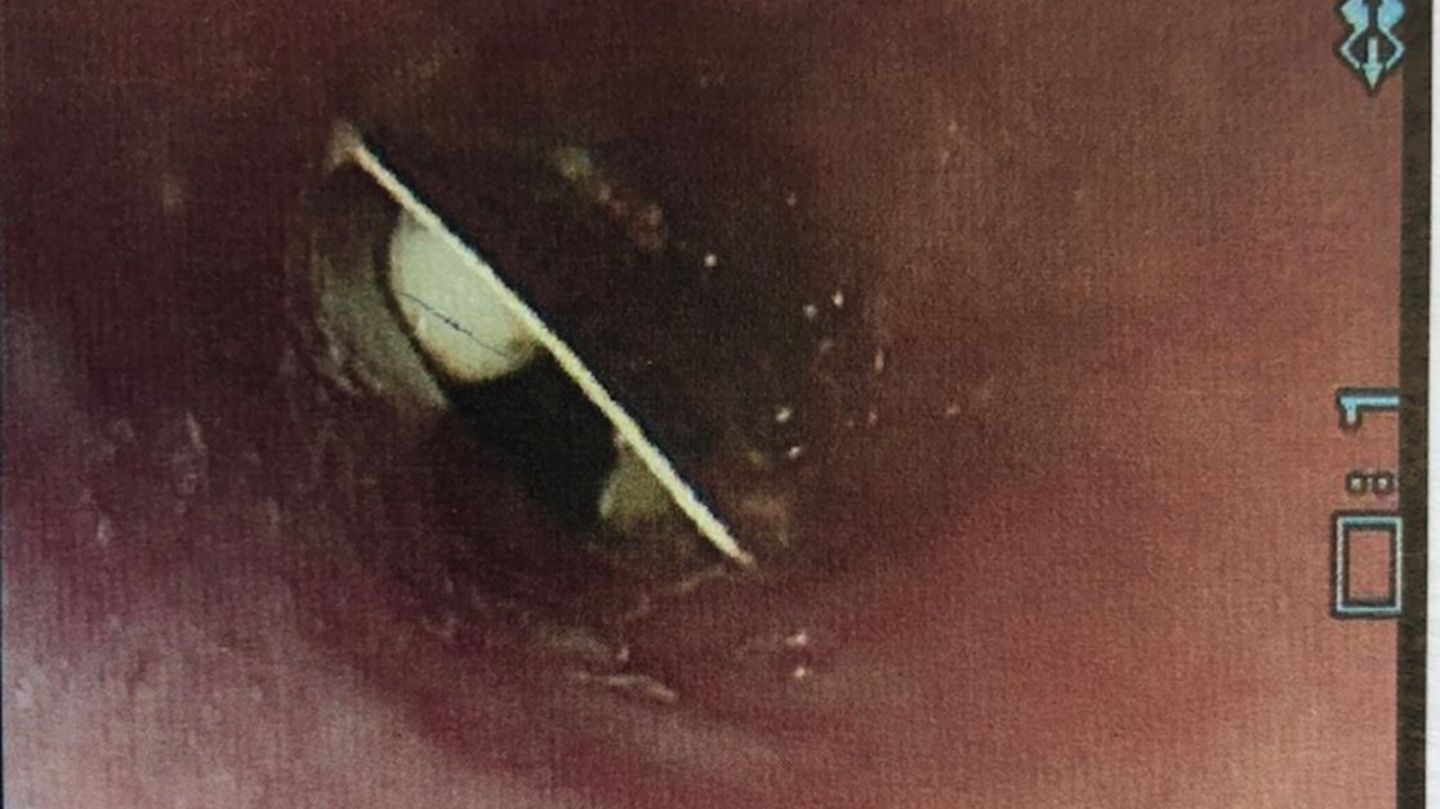

Die Ärzte untersuchten die Speiseröhre mithilfe einer Kamera und entdeckten schließlich die Medikamentenverpackung

Erst nach 17 Tagen und weiteren, erfolglosen Untersuchungen entschlossen sich die Mediziner die Speiseröhre mithilfe eines Endoskops zu untersuchen. Dabei entdeckten sie die Medikamentenverpackung, die im oberen Abschnitt der Speiseröhre steckte und entfernten sie. Über den kuriosen Fall berichten sie im Fachblatt "BMJ Case Reports".